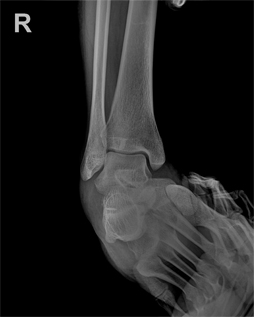

외측 불안정성 수술 후